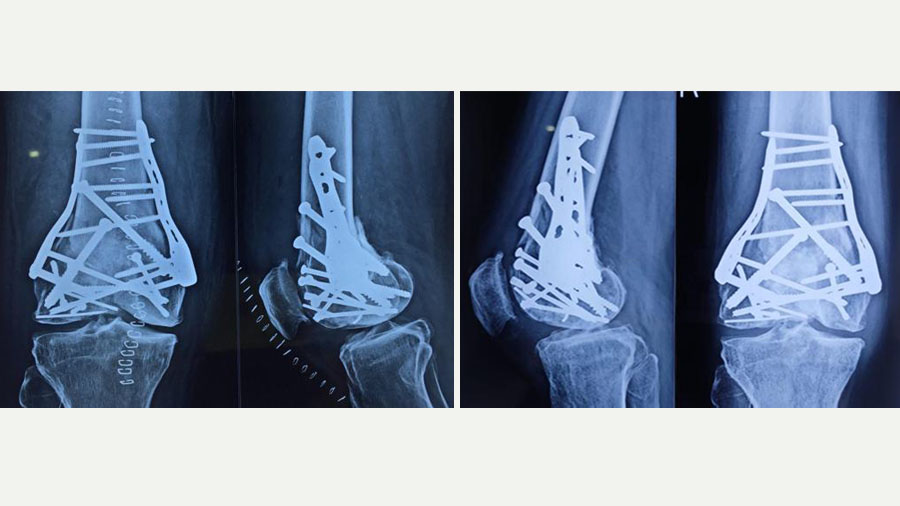

Permanent fixation was then achieved using two plates and multiple screws. Due to the unavailability of a dedicated plate for this particular fracture configuration, we used a shoulder locking plate, which fitted anatomically well for medial and lateral support. This unorthodox but carefully considered decision underscores the importance of improvisation when conventional tools fall short.

Some people may also ask why we did not perform a knee replacement from the outset, given the extent of damage. The answer lies in the nature of the fracture. In a primary knee replacement, only the articular surface is replaced, resting on structurally sound bone. In this case, the bone itself was destroyed.

Had we chosen replacement initially, we would have needed a tumor prosthesis – a bulky, costly, and complex option with a relatively short lifespan and considerable functional restrictions. By reconstructing the native bone, we preserved the possibility of a more standard primary knee replacement in the future, should it become necessary.